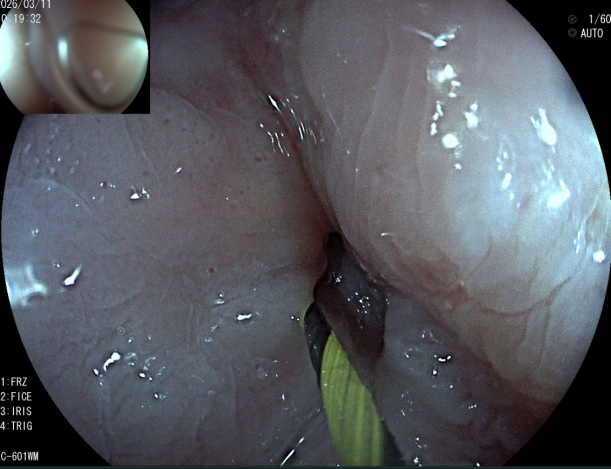

术前、术中、完成造瘘的食管

为破解这一临床难题,医院坚持守正创新,中西医并重。创新利用子镜直视探查+导丝精准引导+扩张+造瘘一体化的零射线术式。手术全程在高清直视下完成,术者能够清晰辨识狭窄通道与黏膜结构,安全引导导丝跨越闭塞段,同步完成食管扩张与经皮胃造瘘,三大技术无缝衔接,一次成型,全程零射线。创伤更小、恢复更快。

与传统术式相比,该技术实现了三大核心突破:一是全程零辐射,患者彻底免除电离辐射损伤,医护告别铅衣负重,更符合绿色微创理念;二是直视更精准,变“盲穿摸索”为“可视化操作”,显著降低穿孔、出血等并发症风险;三是一站式解决,一次手术同步打通进食通道、建立营养通路,快速改善患者营养状况与生活质量。